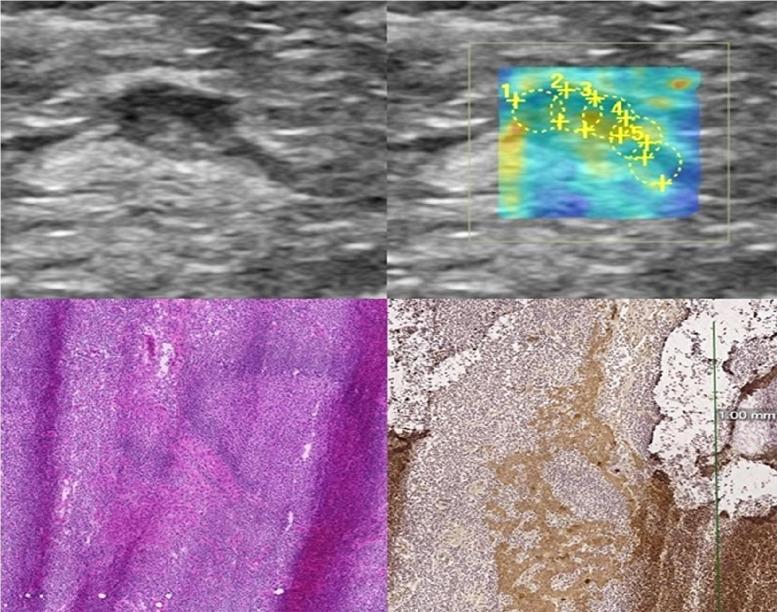

To assess the ability of 2D-Shear wave elastography (2D-SWE) to evaluate its reproducibility, to define the optimal orientation and size of the region of interest (ROI), and to differentiate benign from malignant inguinal lymph nodes (LNs).

Thirty-two suspicious inguinal LNs from 21 patients were evaluated with 2D-SWE. SWE measurements were obtained in two orthogonal planes. To investigate reproducibility, sensitivity and specificity, circular ROIs with a diameter of 1 mm, 2 mm, 3 mm and 5 mm were placed on the cortex of the LNs. Additionally, one freehand ROI was drawn covering majority of the LN. Two observers performed five sets of SWE measurements for each ROI size. All LNs underwent core needle biopsy or were surgically removed.

RESULTS

The 3 mm ROI for Mean-E in axial plane showed high interrater agreement [intraclass correlation coefficient (ICC) 0.899] with the cut-off value of 7.31 kPa resulting in 88.9% sensitivity and 60.9% specificity for differentiating malignant from benign LNs. In benign LNs, mean elasticity of the ROI was lower (7.68 ± 3.82 kPa; range, 3.41-15.40 kPa) compared to the malignant LNs (15.81 ± 10.61 kPa; range, 3.86-36.45 kPa).

CONCLUSIONS

The most reproducible way to measure stiffness in inguinal LNs is a 3 mm circular ROI centered on the cortex of the LN in axial plane. Elasticity values were higher in the malignant LNs reflecting the stiffer nature of the metastatic LNs. 2D-SWE offers a noninvasive ultrasonographic tool to assess superficial inguinal lymph nodes with high reproducibility.